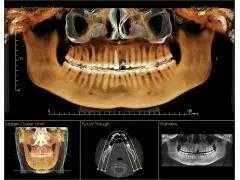

先要做一个口腔全景X光照片,当然颌骨CT会更精确。这是为了查看口腔的具体情况,有没有炎症啊、牙槽骨是否正常啊……然后,医生会了解患者全身的病史,可能需要查血常规、出凝血时间、血压、血糖、乙肝5项等。这些做完后,才会确定种植牙方案。